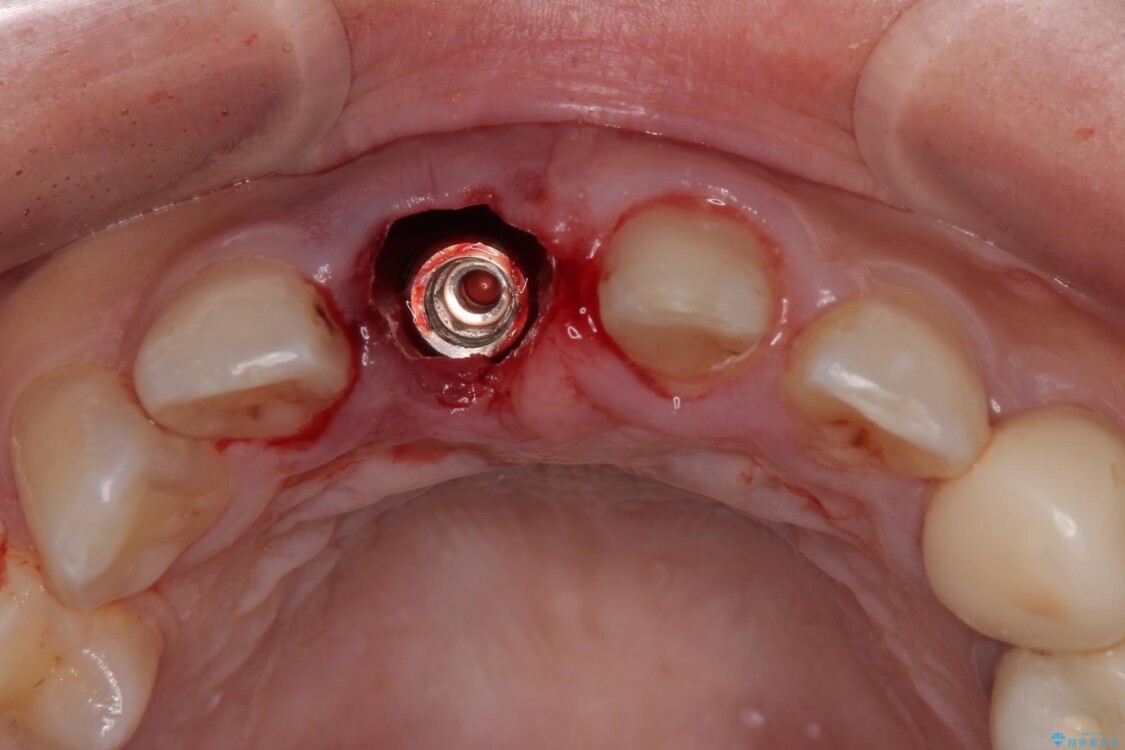

治療途中

• 「抜歯してブリッジ」と言われた20代女性が選んだ治療とは|たった4か月で自然な笑顔に抜歯即時インプラント+審美補綴の症例 治療途中画像

▶右上中切歯

抜歯後、即時インプラント埋入

審美性を考慮し、仮歯を即日装着

治療期間を最小限に抑えつつ、自然な前歯のラインと歯ぐきの形を維持